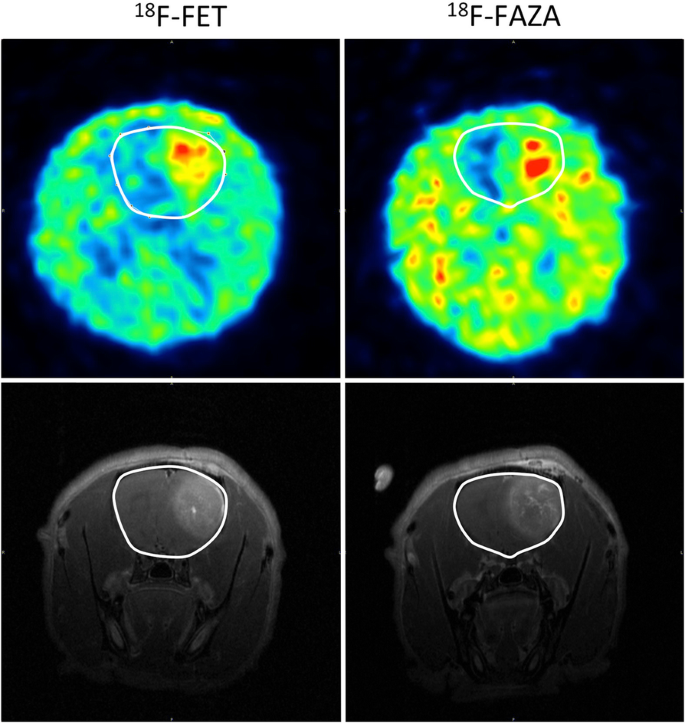

Comparison [18F]FET and [18F]FAZA PET

The uptake of both tracers is increased in the tumor region compared to the surrounding healthy brain tissue (Fig. 4). The SUVmean, SUVmax, TBRmean and TBRmax - values of the [18F]FET and [18F]FAZA pre-RT PET scans were compared using the Mann-Whitney U test (Table 1). The average SUVmean in the tumor was significantly higher for [18F]FET (0.80 ± 0.16) compared to [18F]FAZA (0.10 ± 0.05) (p = 0.024). A significant difference was also found for the average SUVmax as [18F]FET (1.21 ± 0.23) was significantly higher compared to [18F]FAZA (0.16 ± 0.07) (p = 0.024). The average SUVmean, SUVmax values in healthy brain tissue were also significantly higher for [18F]FET (SUVmean 0.45 ± 0.08; SUVmax 0.60 ± 0.09) compared to [18F]FAZA (SUVmean 0.07 ± 0.03; SUVmax 0.09 ± 0.04) (p = 0.024). Likewise, the average TBRmean of [18F]FET (1.79 ± 0.33) was significantly different compared to [18F]FAZA (1.35 ± 0.14) (p = 0.048). However, between the average TBRmax values no significantly difference was found ([18F]FET: 2.72 ± 0.53; [18F]FAZA: 2.23 ± 0.13).

Unfortunately, there are only few studies available that describe the uptake of [18F]FAZA in GB patients or in a GB rat model. In order to characterize the biological features of the F98 GB model, Belloli et al. [41] studied the uptake of [18F]FDG and [18F]FAZA. Contrary to our study, the [18F]FAZA uptake in the study by Belloli et al. was centrally located and showed a TBR value of 2.2 ± 0.4, whereas in our study a lower TBRmean for [18F]FAZA, i.e. 1.35 ± 0.14, was observed. In agreement with the study by Belloli et al., visual analysis of the PET scans with different tracers showed a more centrally located [18F]FAZA uptake in the tumor in comparison to [18F]FET uptake. The latter is in agreement with the knowledge that the most hypoxic tumor regions are centrally located whereas viable tumor cells, surrounding tumor necrosis are situated in the periphery of the tumor. As described by several research groups both [18F]FET and [18F]FAZA are suitable PET tracers for the purpose of sub-volume boosting [41, 42].

In agreement with the histological findings, GB is characterized by central tumor necrosis with a viable and rapidly infiltrating tumor rim whereas hypoxic regions are observed in the middle of the tumor and regions with elevated amino acid transport are detected at the border of the tumor [19].